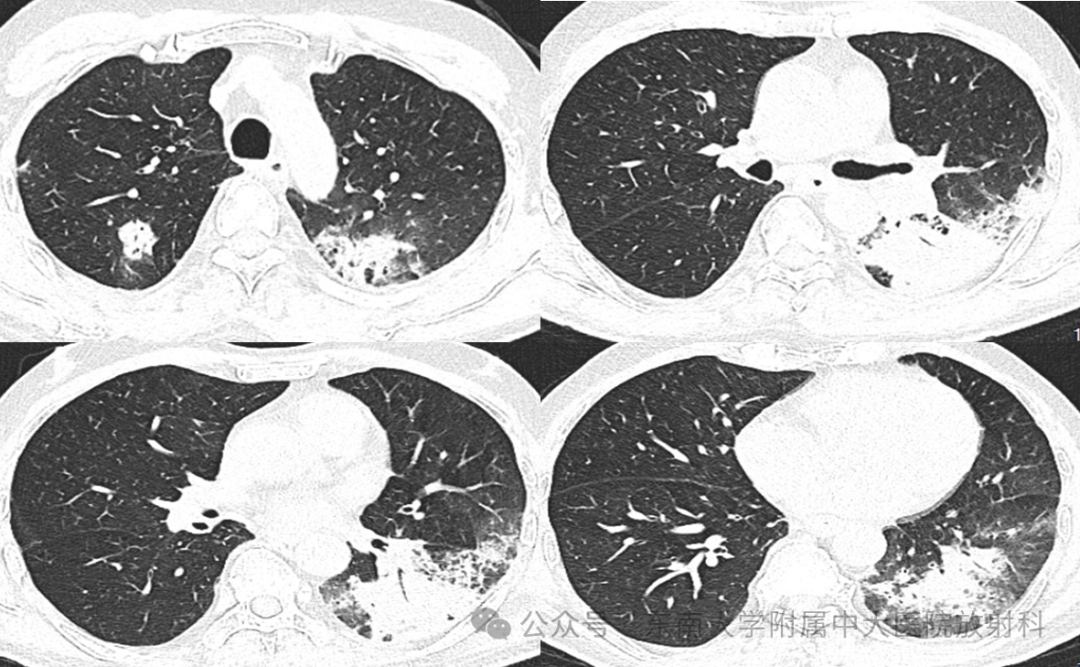

从影像学看机化性肺炎的特征

• 现病史:患者2年前(2023-10)确诊食管癌,予以依托泊、顺铂、斯鲁利单抗治疗,病情稳定后患者斯鲁利单抗免疫维持治疗。2024-9-21外院复查CT提示两下肺纵隔旁炎症,暂停免疫治疗。2024-12-02外院CT复查CT示两肺部分病灶较前吸收好转,部分较前明显或新见;2024-12-04号来我院住院治疗,支气管镜(左下叶前基底段活检)病理提示炎症伴机化,予以甲泼尼龙治疗症状好转后予以出院,2025-01-07复查CT提示两肺病灶明显吸收降;2025-04-12、05-03、05-24共3次使用斯鲁利单抗免疫治疗,患者06-10起出现咳嗽咳痰伴胸痛,06-17外院CT示左肺下叶炎症,后至我院住院,予哌拉西林钠他唑巴坦钠感染治疗;07-02复查胸部CT,病灶吸收不明显,建议患者行气管镜治疗,患者考虑后表示暂不行气管镜,要求出院(出院带药奈诺沙、溴己新)。出院后仍有反复咳嗽,08-12再次我院就诊

2025-07-02 CT

图片

2025-08-12 CT